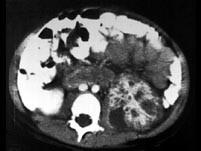

问题 男,5岁,有尿路感染伴急性发热,CT增强扫描如图所示,最可能诊断为 ( )

选项 A、左侧黄色肉芽肿性肾盂肾炎 B、左侧慢性肾盂肾炎 C、左侧肾脓肿 D、左侧急性肾盂肾炎 E、左侧肾炎

答案 D